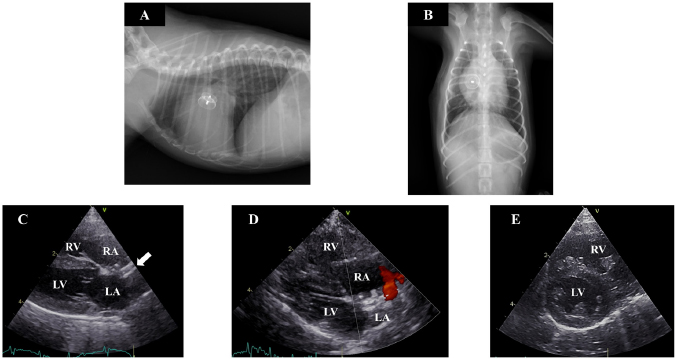

Five days after the operation, dilatation and concentric hypertrophy of the RV, ventricular septal flattening, pulmonary overcirculation, and main pulmonary artery enlargement were improved (pulmonary artery-to-aorta ratio: 1.05) (Fig. 2a–e) although mild residual shunting was observed (Fig. 2d). At 10 months after the operation, the dog had gained weight (1.74 kg), RV enlargement was further improved, and the Qp/Qs had decreased to 1.16.

Fig. 2. Thoracic radiography and echocardiography 7 months after the operation. (a) and (b): In thoracic radiography, the device was clearly visible and there was no evidence of pulmonary overcirculation. (c)(e): The device was appropriately positioned across the defect (solid arrow), and the right atrial and ventricular volume overload had almost resolved although mild residual shunting was observed. Ventricular septal flattening was also improved. (LA): left atrium; (LV): left ventricle; (RA): right atrium.